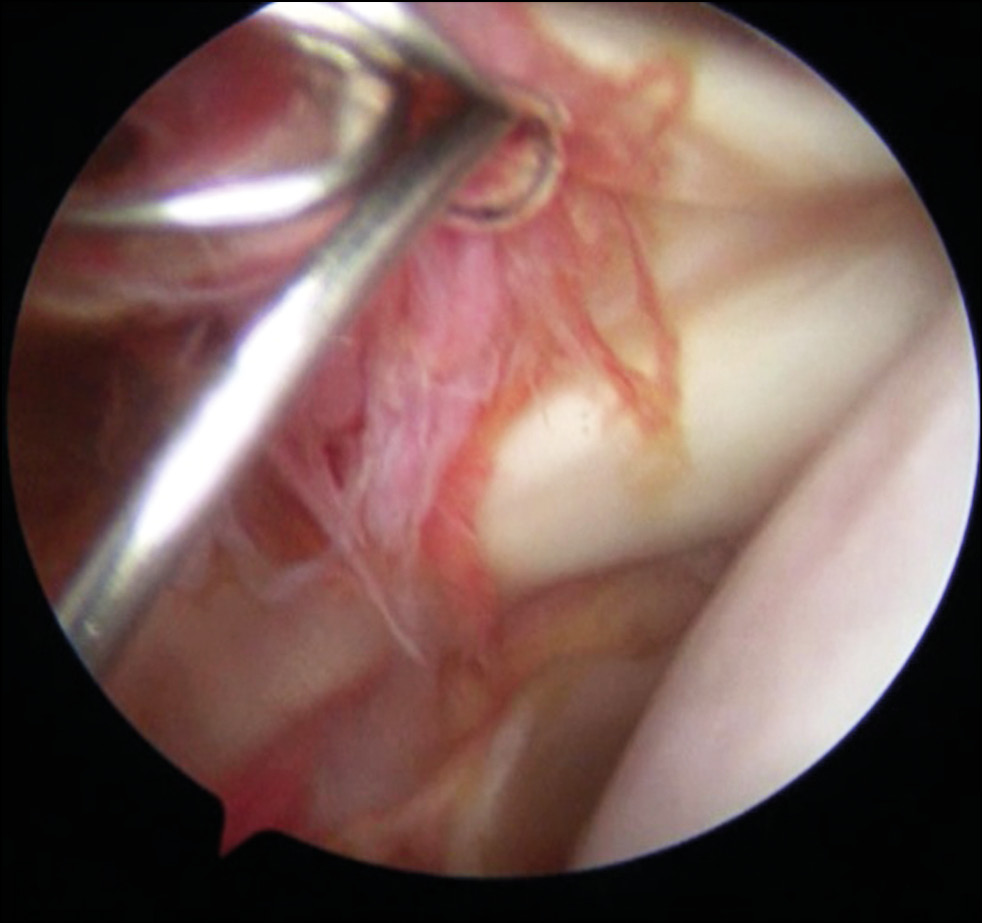

In Stage 2, the arthroscope was transferred to the anterior port, and the main nerves (n. axillaris and n. musculocutaneus) were visualized (Fig. 6). The area of damage to the articular surface of the scapula and the lower edge of the coracoid process were decorticated until pinpoint bleeding appeared (Fig. 7), thereby reducing the risk of bone autograft splitting during its collection, and increasing the contact area, congruence between the cavity of the scapula and the coracoid process (Fig. 8).

Fig. 6. Isolation of the axillary nerve (n. axillaris).